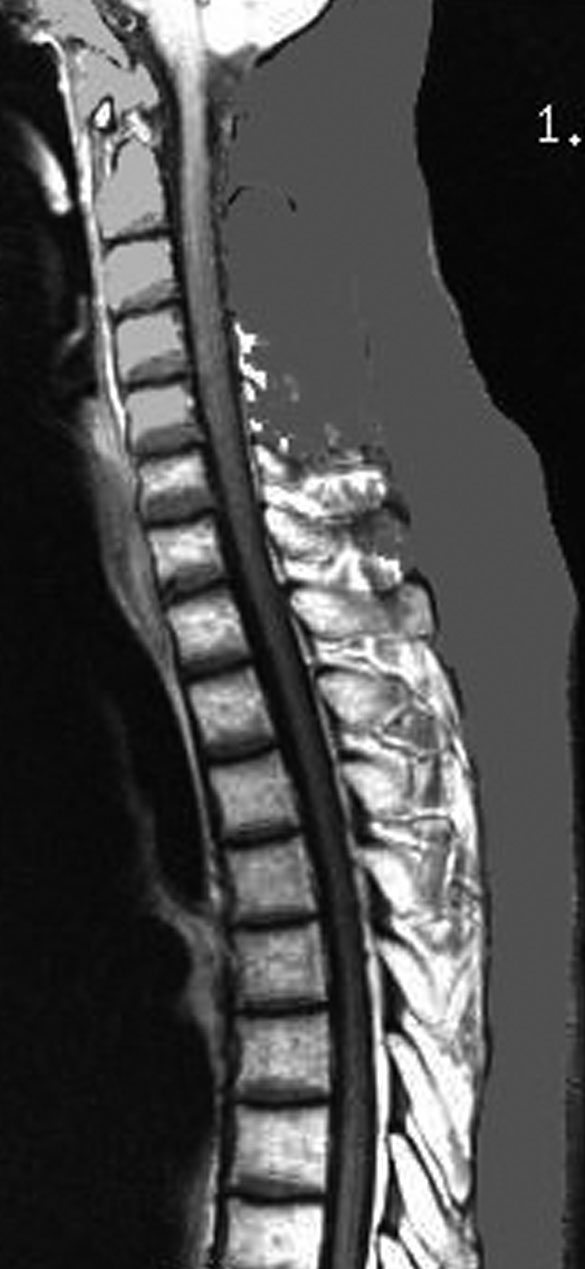

20歳くらいから尿崩症があり,2年後に汎下垂体機能低下症と軽度の認知機能低下を生じました。脳室壁と松果体,神経下垂体にジャーミノーマが広がっているのですが,脊髄背面と脳幹部の周囲にも腫瘍結節が見られました。脳室上衣以外の部位に腫瘍があるので,播種を疑いました。ジャーミノーマの播種というのは実際にはとても珍しくてなかなかみないものです。HCGは軽度の上昇,鼻孔から下垂体部分を生検して病理確定診断して,化学療法と脳脊髄照射 25.2Gy をしました。腫瘍は1コース目の化学療法でほとんど消失したので,他の組織型の悪性混合性胚細胞腫瘍ではないと考えられます。

脊髄にも再発は見られませんでした。